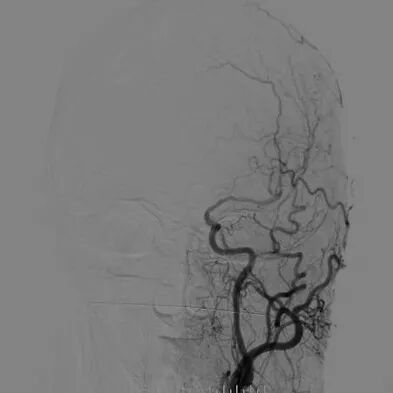

心脑联合造影

-- 右侧颈内起始部中度狭窄,经前交通向左侧代偿

-- 左侧颈内起始部重度狭窄

-- 右侧椎动脉起始部中度狭窄

-- 左侧椎基底动脉无明显异常

-- 冠脉多发狭窄